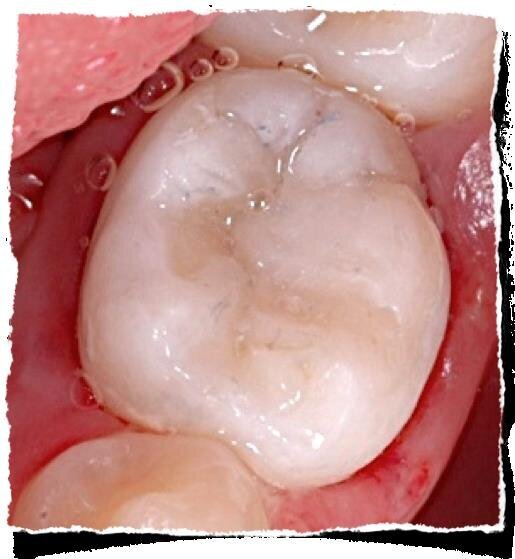

Un sanguinamento profuso dopo 3 minuti da una indicazione di iperemia pulpare ed è consigliabile procedere ad un trattamento di pulpectomia. Ottenuta una adeguata emostasi, senza sostanze promuoventi, si procede al posizionamento in camera pulpare del materiale scelto. Nel tempo sono stati utilizzati svariati materiali, come il formocreosolo e la glutaraldeide, che però non vengono più utilizzati per la loro cancerogenicità. Attualmente i migliori in commercio per un trattamento di pulpotomia sono i cementi Portland, gli MTA ed i materiali bioceramici.

Dalla letteratura si evince come questi materiali diano una buona risposta tissutale con delle percentuali di successo, a medio e lungo termine, di circa il 90-98%. In base al tipo utilizzato si potrà procedere, nella stessa seduta o nella successiva, alla ricostruzione definitiva, utilizzando i sistemi adesivi presenti in commercio e materiale composito.